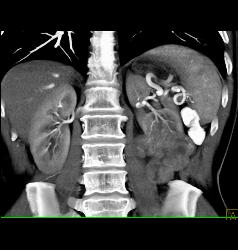

Renal Cell Carcinoma With Paraaortic Adenopathy